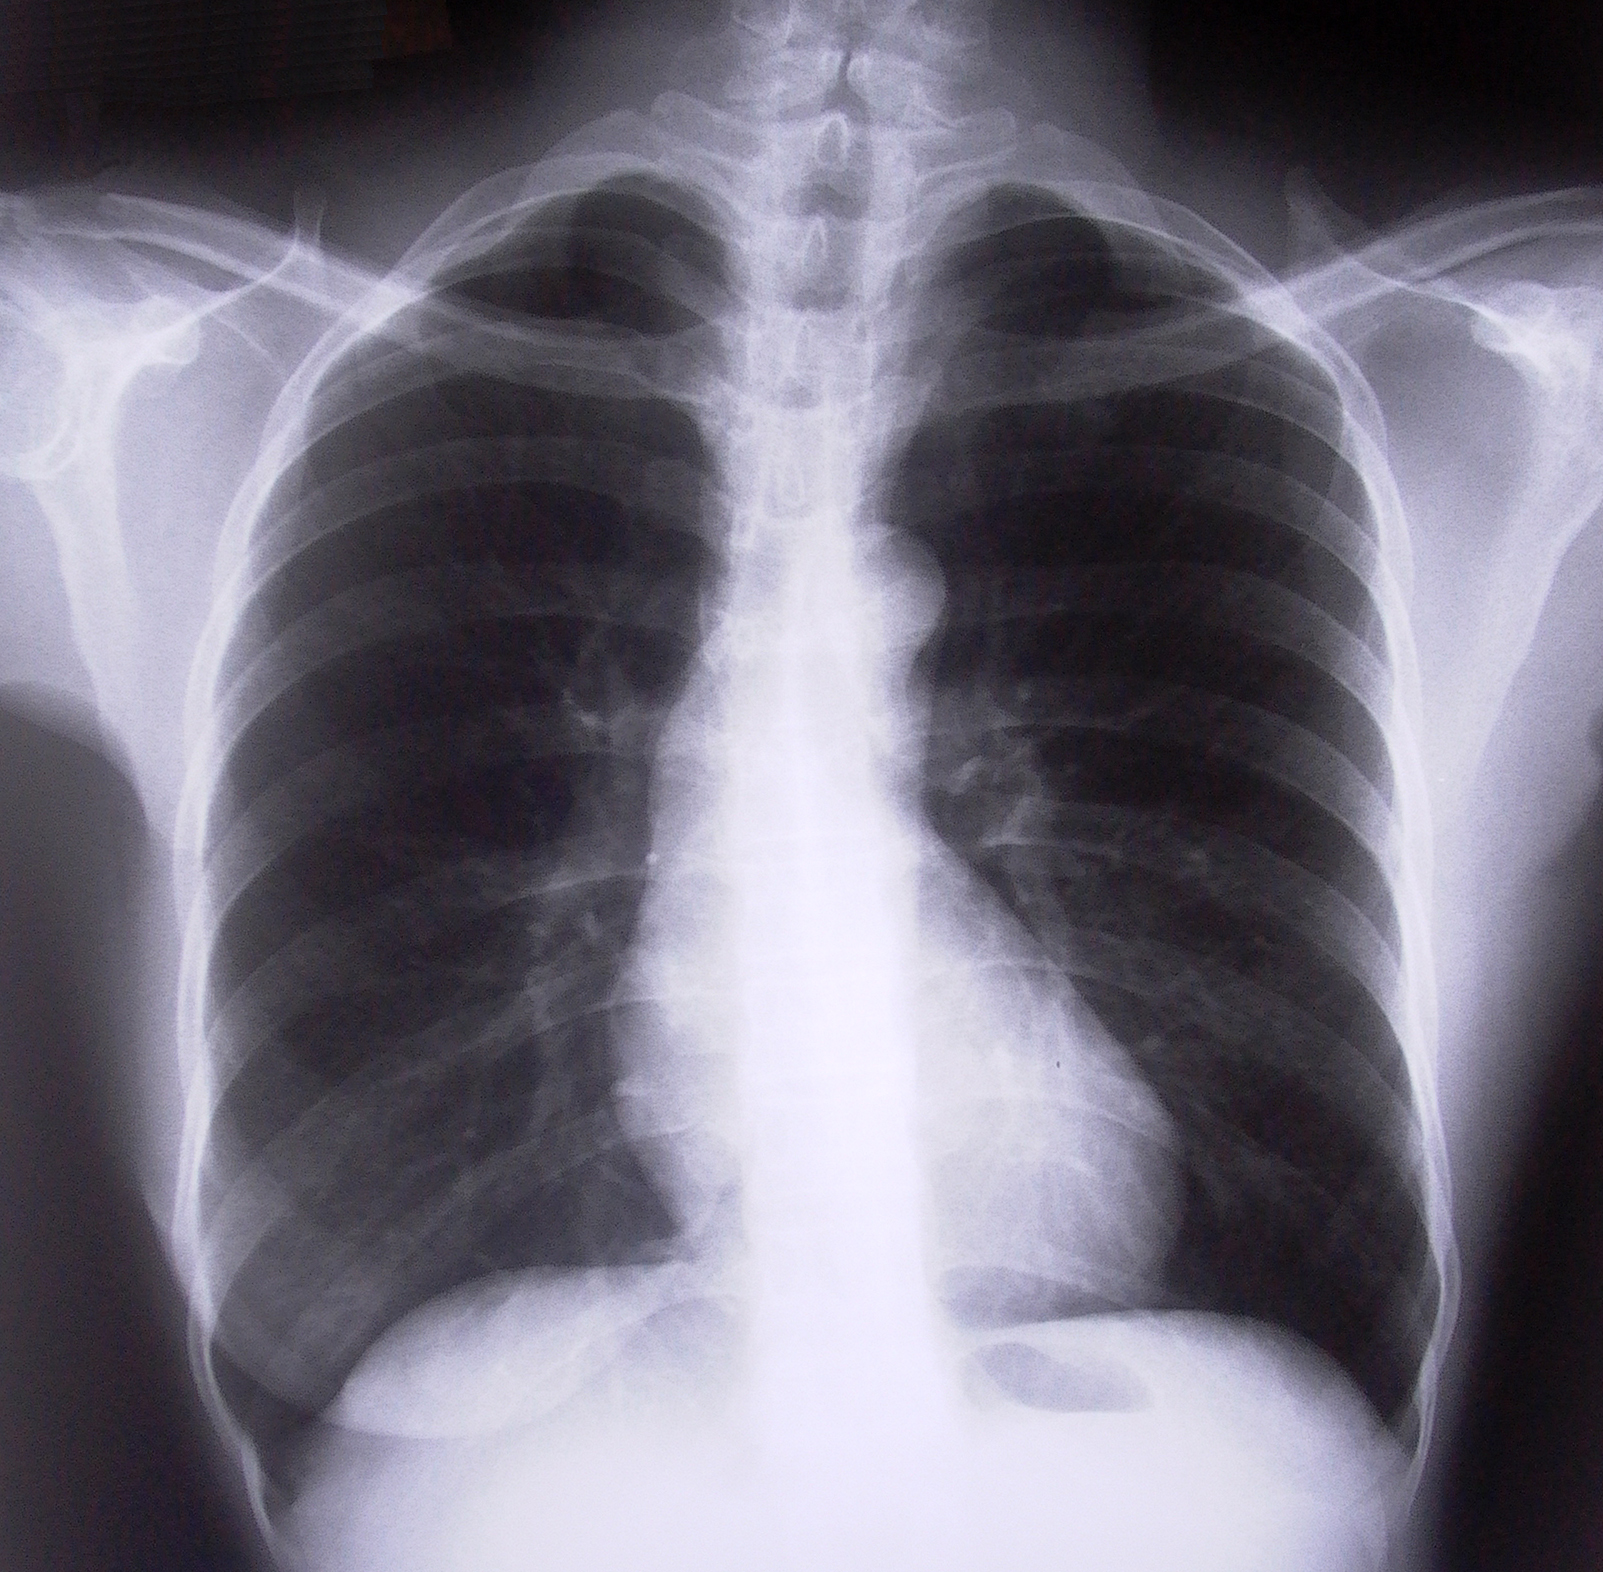

Radiology